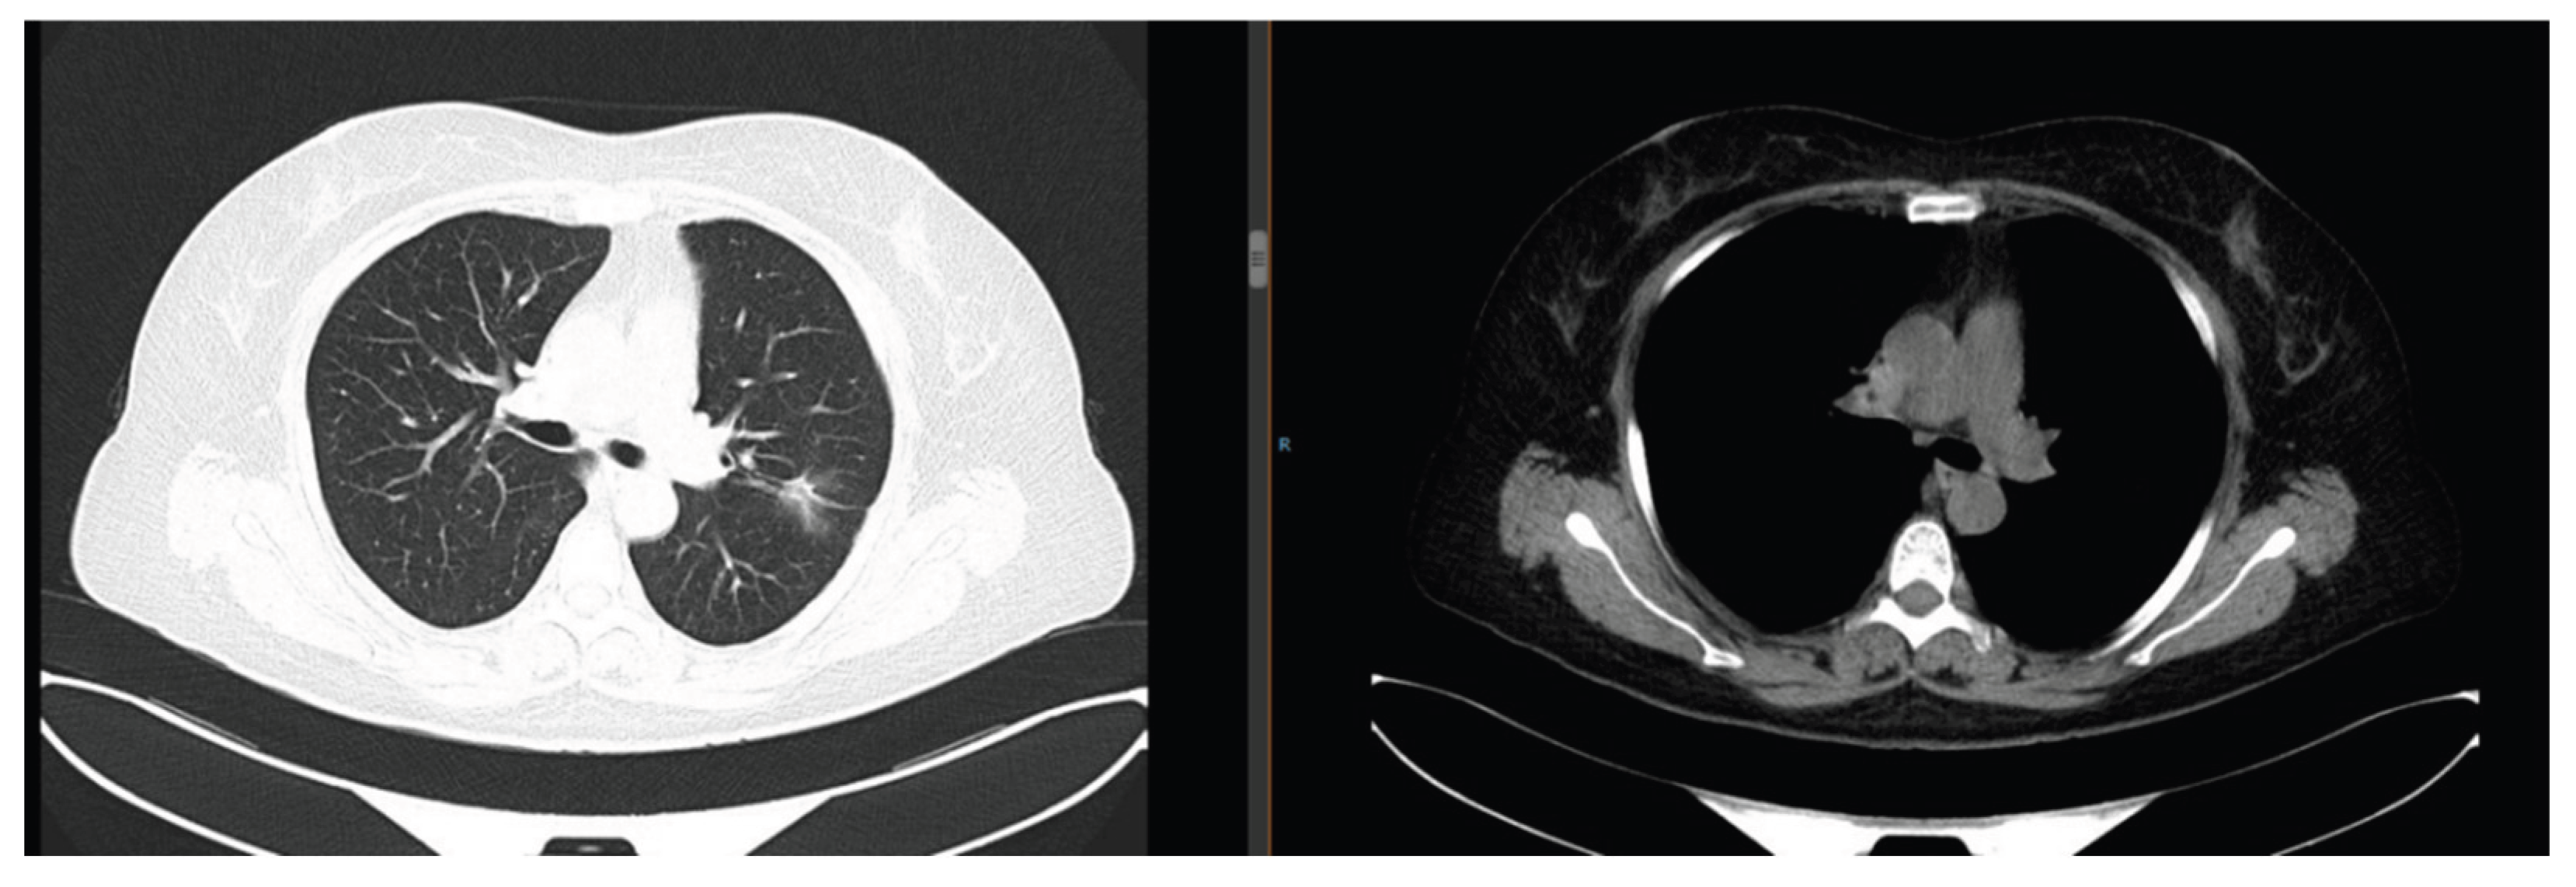

Sixteen months after gefitinib treatment, the pulmonary nodules enlarged (maximum diameter: 4.2 cm) with new lesions (Figure 4), indicating TKI resistance. Repeated biopsy and NGS detected a RET fusion mutation. Due to financial constraints, she refused cabozantinib (a RET inhibitor) and received 6 cycles of pemetrexed + carboplatin chemotherapy combined with anlotinib (anti-angiogenic therapy). The disease remained stable (SD), followed by anlotinib maintenance therapy for 19 months.

Cough and expectoration aggravated, with increased pleural effusion and enlarged abdominal lymph nodes (Figure 5). She initially refused treatment, leading to disease progression. In April 2023, she underwent right pleural effusion drainage + bevacizumab intrapleural perfusion, combined with 1 cycle of paclitaxel (240 mg ivgtt d1) + nedaplatin (50 mg ivgtt d1-2) chemotherapy. Third NGS detected an EGFR T790M mutation, and she was switched to the third-generation TKI osimertinib (80 mg orally once daily). As of July 2025, the pulmonary lesions remained stable (maximum diameter: 2.1 cm) (Figure 6).

Figure 4. Chest CT on January 16, 2021: Enlargement of pulmonary nodules (maximum diameter 4.2 cm) with new lesions.

Figure 5. Chest CT in January 2023: Increased pleural effusion and enlarged abdominal lymph nodes.

Figure 6. Chest CT in July 2025: Stable pulmonary lesions (maximum diameter 2.1 cm).